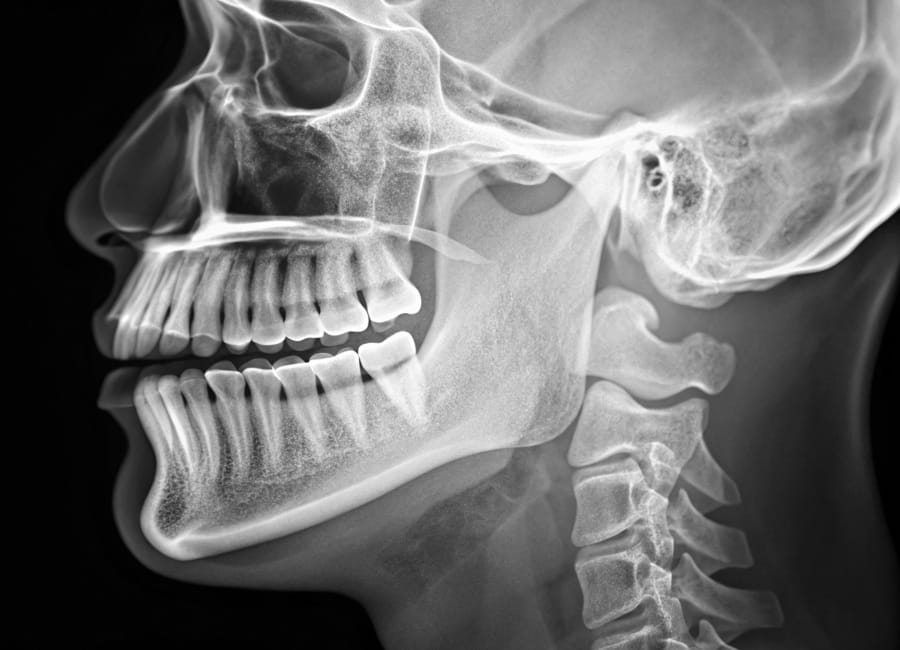

Digital X-rays

Digital X-ray technology uses digital sensors and a computer to create detailed, high-quality images of your teeth and gums.

Dr. Isaac will review these images to assess the position of your teeth beneath the gums and evaluate the surrounding bone structure. This helps diagnose your orthodontic condition accurately. Additionally, the X-rays can reveal important factors that may impact your treatment, such as developing tooth decay or existing dental restorations. All of this information is essential for diagnosis and effective treatment planning.